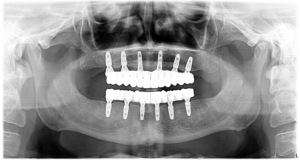

În timpul intervenției, i-au fost inserate 6 implanturi în mandibulă și 6 în maxilar, pentru a susține o dantură completă de care se bucură în prezent.